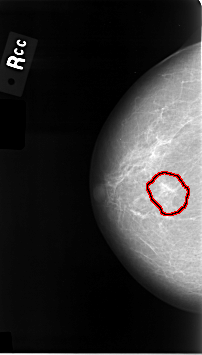

C_0014_1.RIGHT_CC

FILE: C_0014_1.RIGHT_CC.OVERLAY

TOTAL_ABNORMALITIES 1

ABNORMALITY 1

LESION_TYPE MASS SHAPE IRREGULAR MARGINS ILL_DEFINED

ASSESSMENT 5

SUBTLETY 4

PATHOLOGY MALIGNANT

TOTAL_OUTLINES 1

BOUNDARY